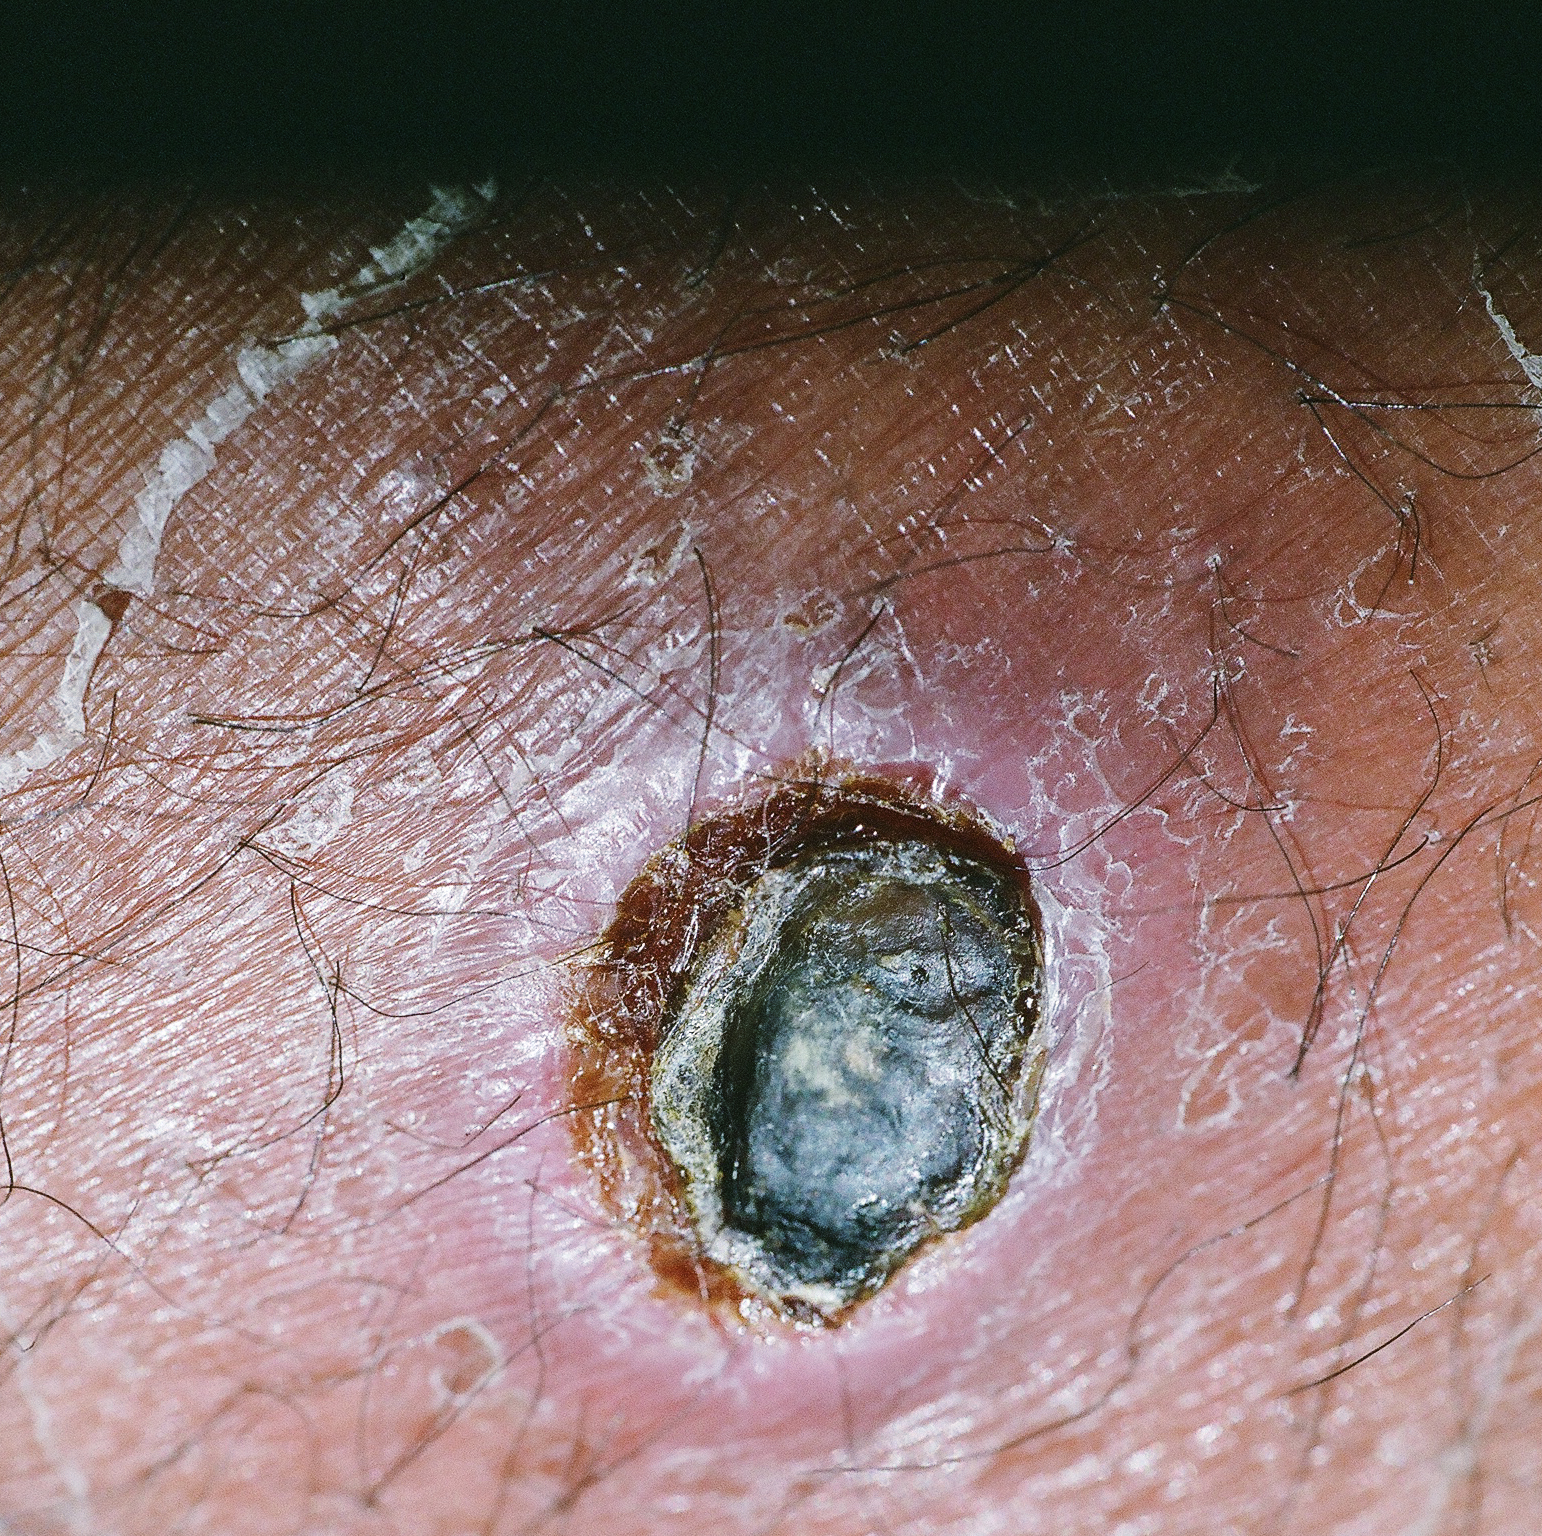

Selected chemigrams and photographs from Honest Orifice, 2018